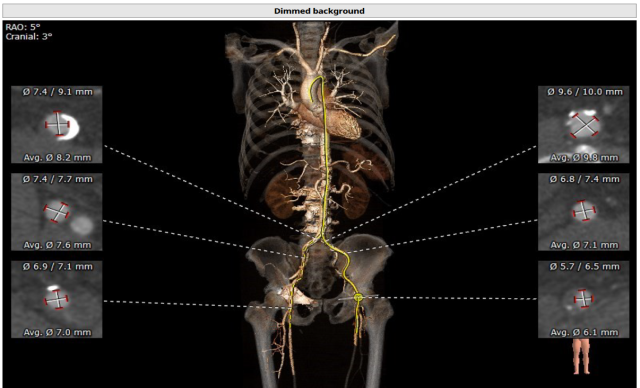

77 岁的男性患者徐某因“劳力性呼吸困难1年余,晕厥2月”就诊于我院心内科并住院接受治疗,入院超声心动图检查发现:主动脉瓣钙化,重度狭窄, 轻度关闭不全,LVEF 50%。诊断为症状性重度主动脉瓣狭窄明确,判断患者符合TAVR 手术指征,无明确手术禁忌症。完善术前CT检查提示(如下图):

佘飞医师及薛亚军医师反复阅读超声及CT评估结果,与张萍教授、王伟民教授、吴永健教授讨论病情后,综合评估结果,决定行TAVR 手术,采用22mm球囊预扩张主动脉瓣,植入26mm Venus-A 瓣膜。通过充分的术前评估与准备,与患者家属反复沟通、告知病情以及相关风险,最终获得家属的手术同意。